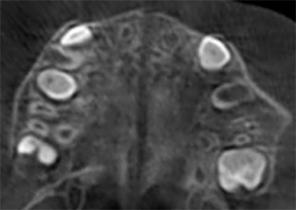

Report sul Caso 2

7 anni 11 mesi 24 fasi di Invisalign® Palatal Expander

Per gentile concessione del Dr. David R. Boschken

Pre espansione Invisalign Palatal Expander

Post espansione Invisalign Palatal Expander

Dopo il trattamento con Invisalign Palatal Expander